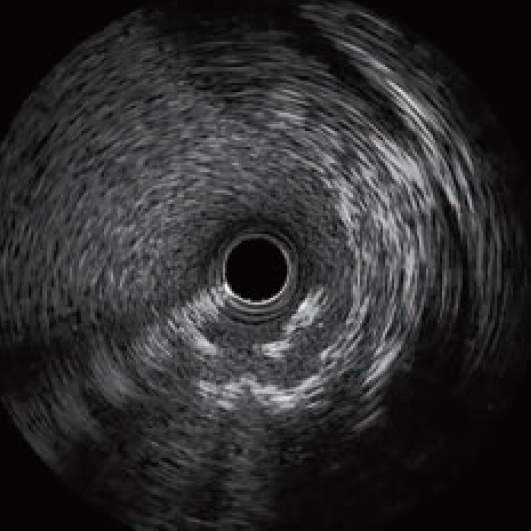

理想支架植入状态

识别技巧

根据 ULTIMATE研究结果理想支架植入效果表现为支架尺寸长度选择合适,充分覆盖病变,近远段支架边缘斑块负荷小于50%;扩张充分支架内最小面积≥5mm2或者最小支架面积大于远端参考管腔面积的90%,无>3mm深达中膜的夹层。

没有支架断裂发生、没有支架内血栓发生、没有明显斑块脱垂、没有支架贴壁不良、没有支架变形、支架对称性大于0.8。